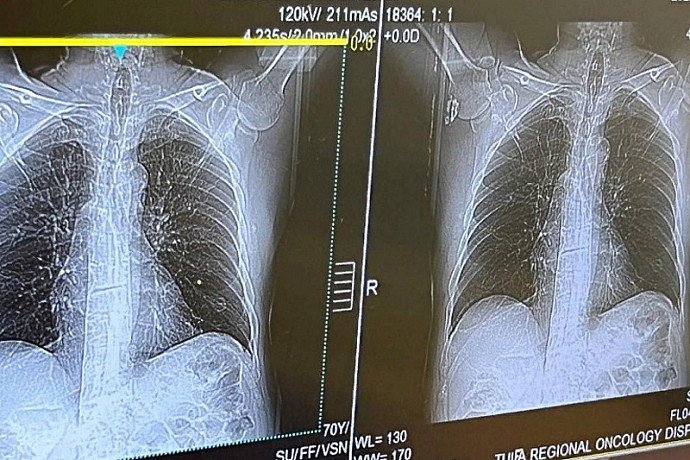

Фото: министерство здравоохранения Тульской области

240 туляков прошли диагностику на наличие злокачественных новообразований в рамках Дня открытых дверей 26 ноября в поликлинике Тульского областного клинического онкологического диспансера.

Жители Тульской области прошли раннюю диагностику онкологических заболеваний, курильщики со стажем сделали низкодозную компьютерную томографию легких.